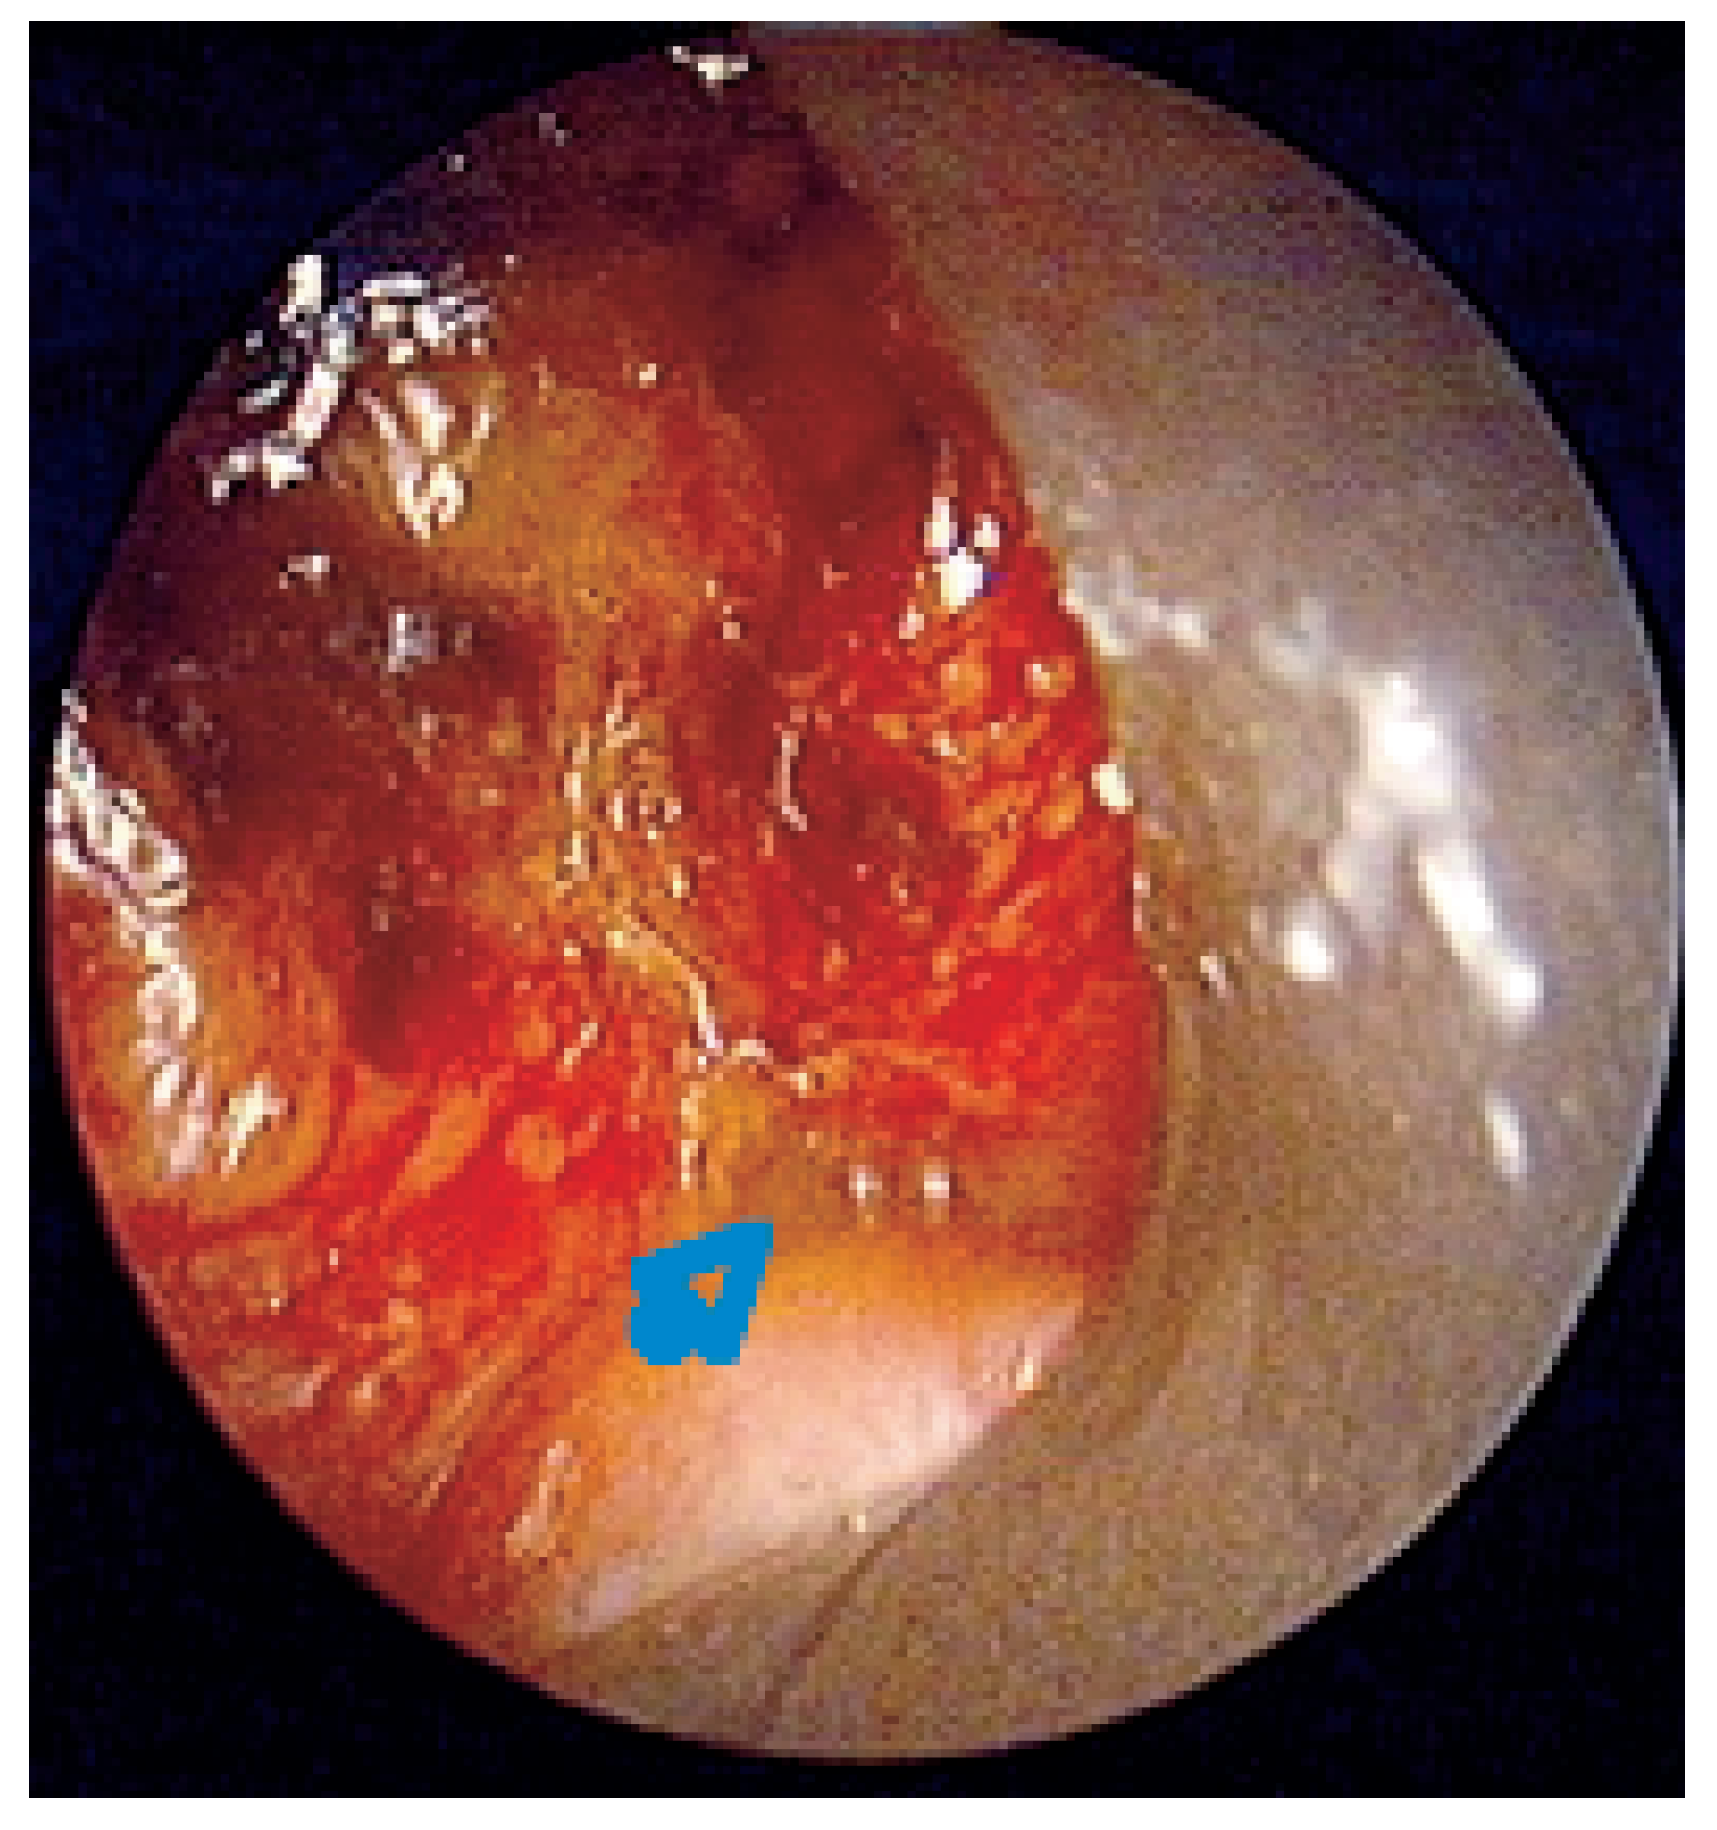

Abbildung 6. Überschichtung eines unbeschichteten Nitionol-Stents durch Granulationsgewebe.

Diese Prothesen bestehen aus Metallgeflechten, die in zusammengefaltetem Zustand in die Atemwege eingebracht und dort entfaltet werden oder sich nach der Freisetzung selbst entfalten und so als künstliche Gerüste dienen. Da ihre Wandstärke wesentlich geringer ist als die der Kunststoffprothesen, bleibt für das Lumen wesentlich mehr Raum. Ausserdem sind sie wesentlich leichter zu implantieren. Die selbstexpandierenden Prothesen entfalten sich durch die geometrische Expansionskraft der Stahlfilamente, aus denen sie aufgebaut sind (Gianturco-Stent und WallStent), oder durch den Memory-Effekt sog. «intelligenter» Metallegierungen aus Nickel und Titan, Nitinol genannt (Ultraflex-Tracheobronchial-Stent), der sie immer wieder in eine einmal vorgegebene Form zurückkehren lässt (Abb. 4 and Abb. 5). Die Hysteresekurve letzterer sog. «memory-shape alloys» ähnelt derjenigen des Knorpels sehr stark, während die Stahlfilamente wegen ihrer Rigidität erhebliche Traumata setzen können, bis hin zur Perforation mit Fistelbildung oder Arrosionsblutung aus der Pulmonalarterie. Auch die selbstexpandierenden Maschendrahtprothesen können von Granulationsoder Tumorgewebe durchwachsen werden (Abb. 6) und sind dann nach interner Reokklusion kaum noch zu entfernen. Aus diesem Grund wurden beschichtete Hybride konstruiert, bei denen das Metallgeflecht von einer gewebeundurchlässigen biokompatiblen Kunststoffmembran umhüllt werden (Abb. 4) [17,18].